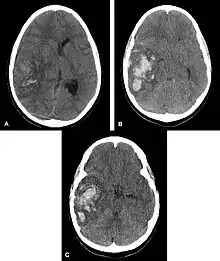

| Intraparenchymal hemorrhage | |

| Multiple intraparenchymal hemorrhage | |

Intraparenchymal hemorrhage (IPH) is one form of intracerebral bleeding in which there is bleeding within brain parenchyma. The other form is intraventricular hemorrhage (IVH).[1]

Intraparenchymal hemorrhage accounts for approximately 8-13% of all strokes and results from a wide spectrum of disorders. It is more likely to result in death or major disability than ischemic stroke or subarachnoid hemorrhage, and therefore constitutes an immediate medical emergency. Intracerebral hemorrhages and accompanying edema may disrupt or compress adjacent brain tissue, leading to neurological dysfunction. Substantial displacement of brain parenchyma may cause elevation of intracranial pressure (ICP) and potentially fatal herniation syndromes.